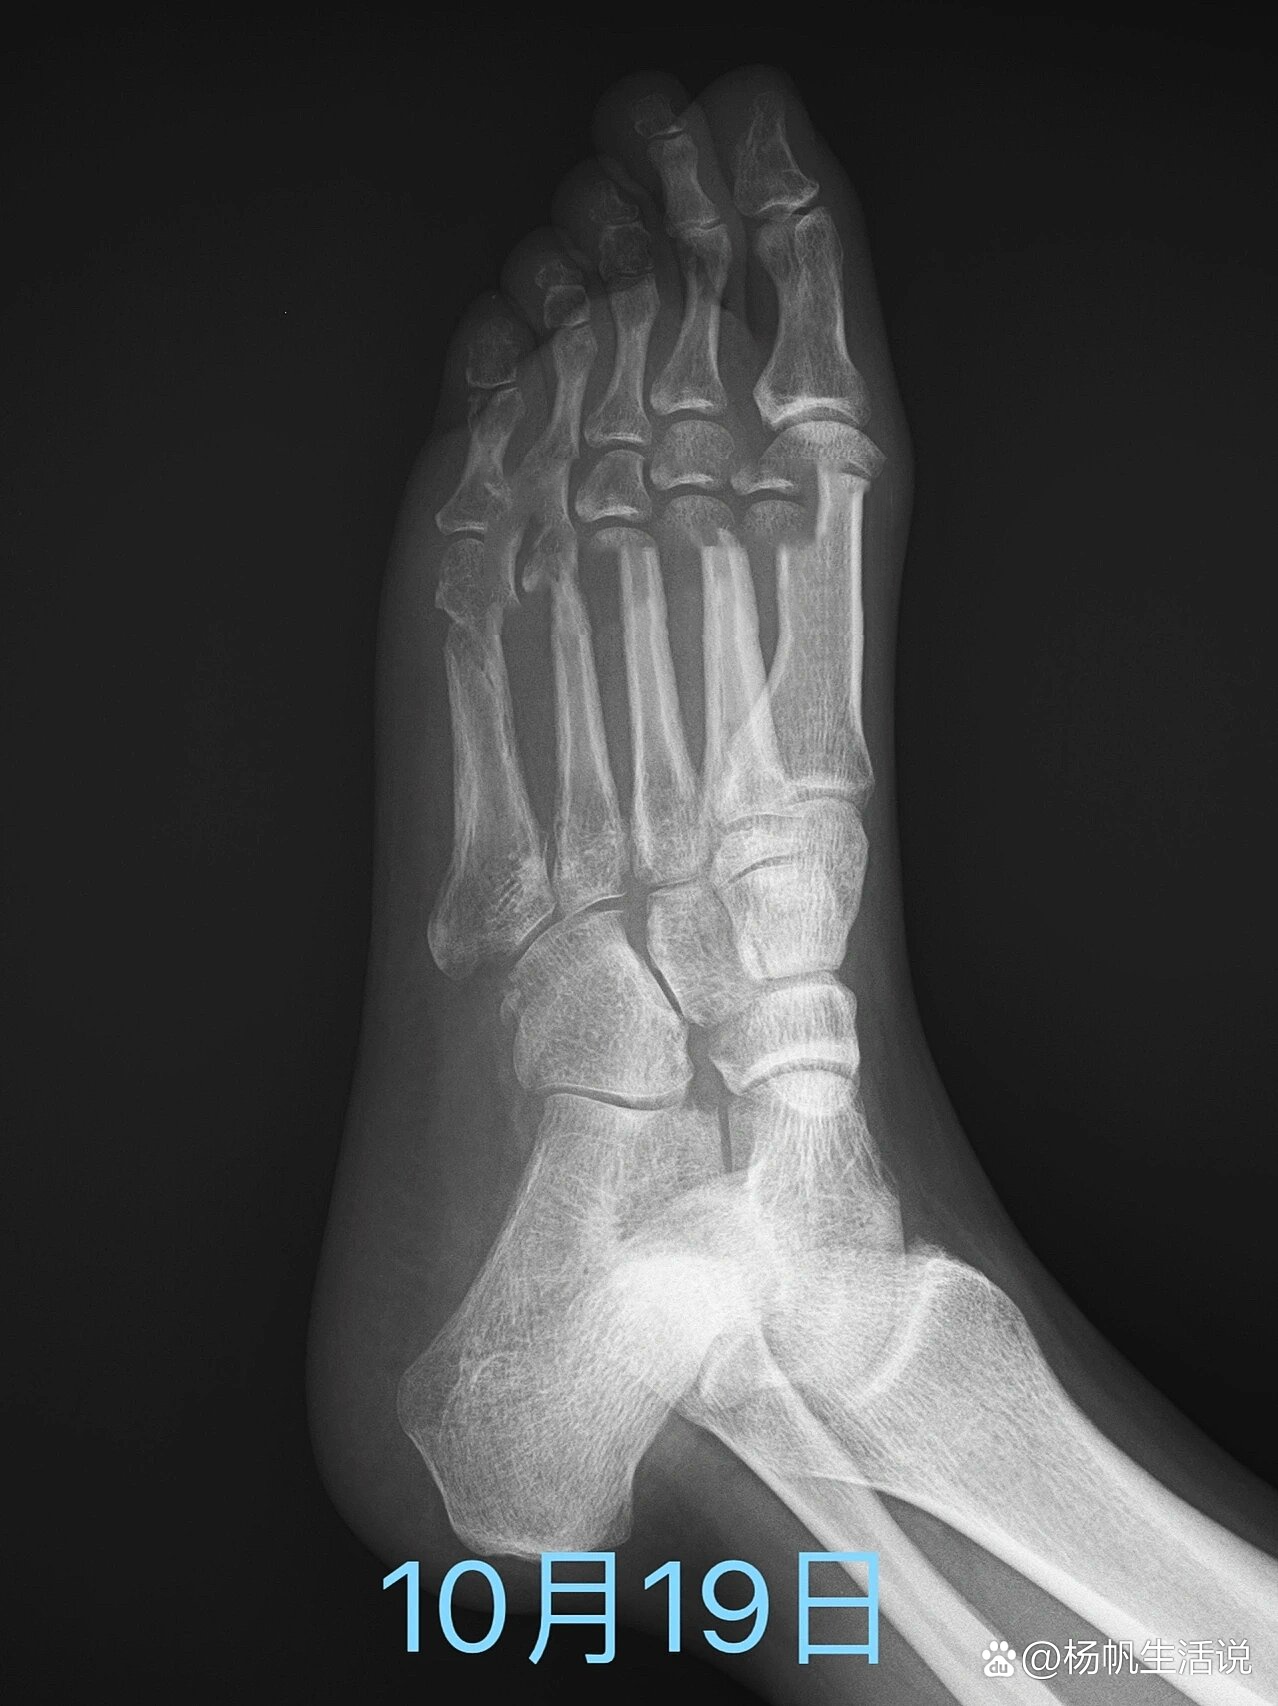

第五跖骨粗隆骨折

前足扭伤导致第五跖骨基底骨折,断端分离移位 - 抖音